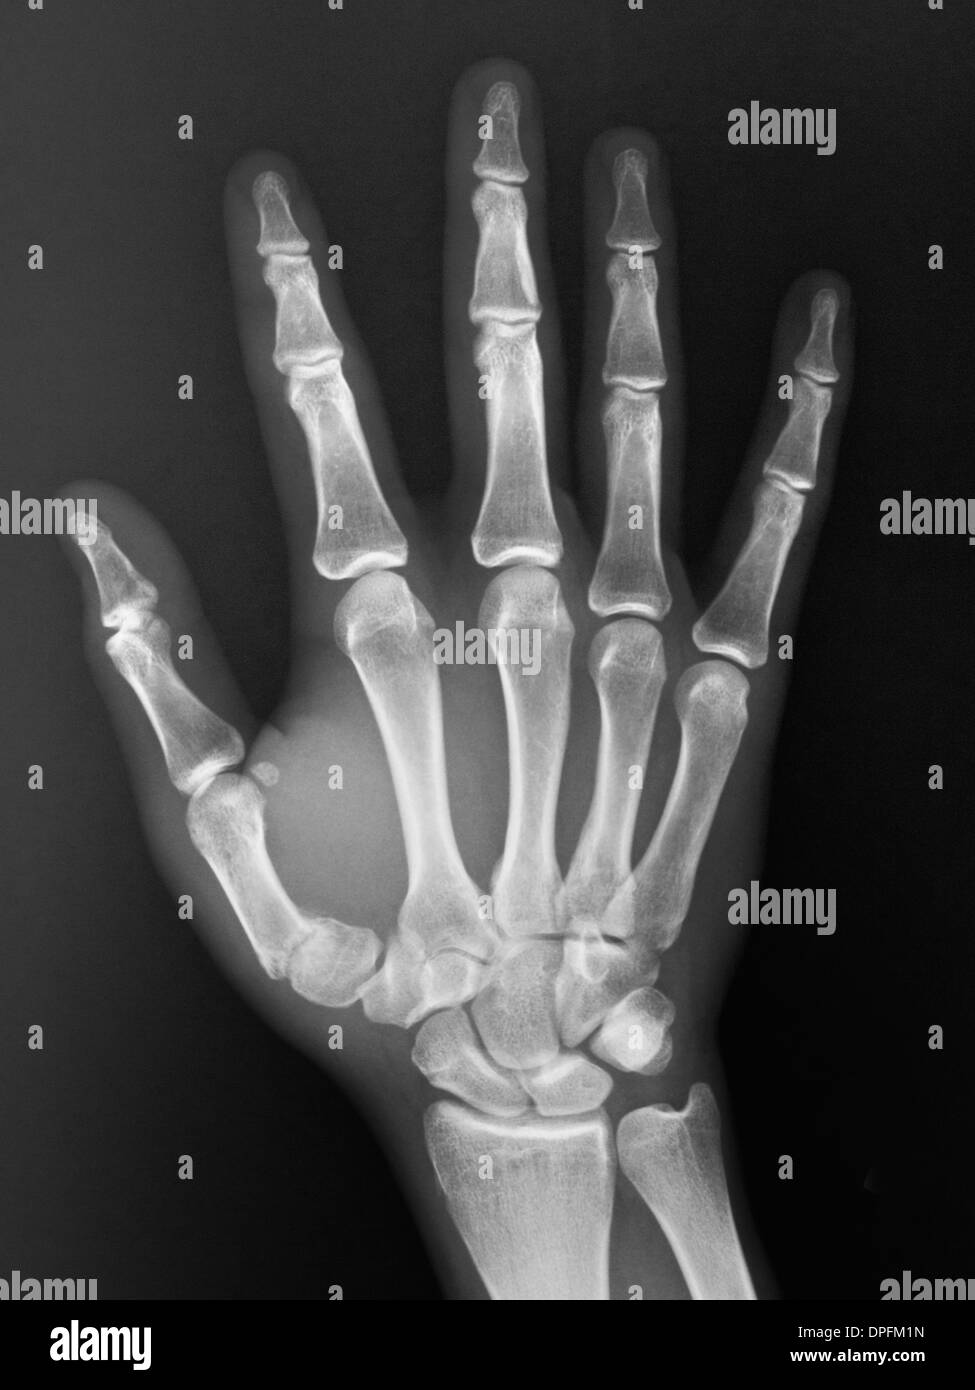

I had an appointement with my doc to get my xray prescription this morning and an appointement for the xray 30 mins ago and I officially have my wrist xray

Can you guys tell me the state of my plates pretty please ?

Pretty sure it's over but hey, gotta get a few opinions before (5'6 late 16m btw)